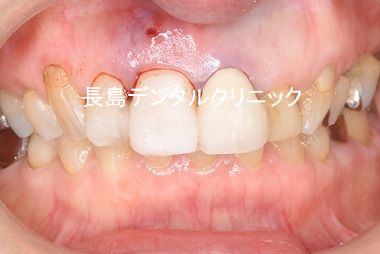

1,インプラント埋入前

片道通院時間2時間かけて来院される患者様です。右上前歯(青い矢

印)の部分が歯根破折を起こし、顎自体も細く前医ではインプラント

治療はできないと断れた患者様です。診察してみるとが歯茎が腫れて

います。(黄色い丸印)通常ならば、抜歯をして数か月後に骨が薄い